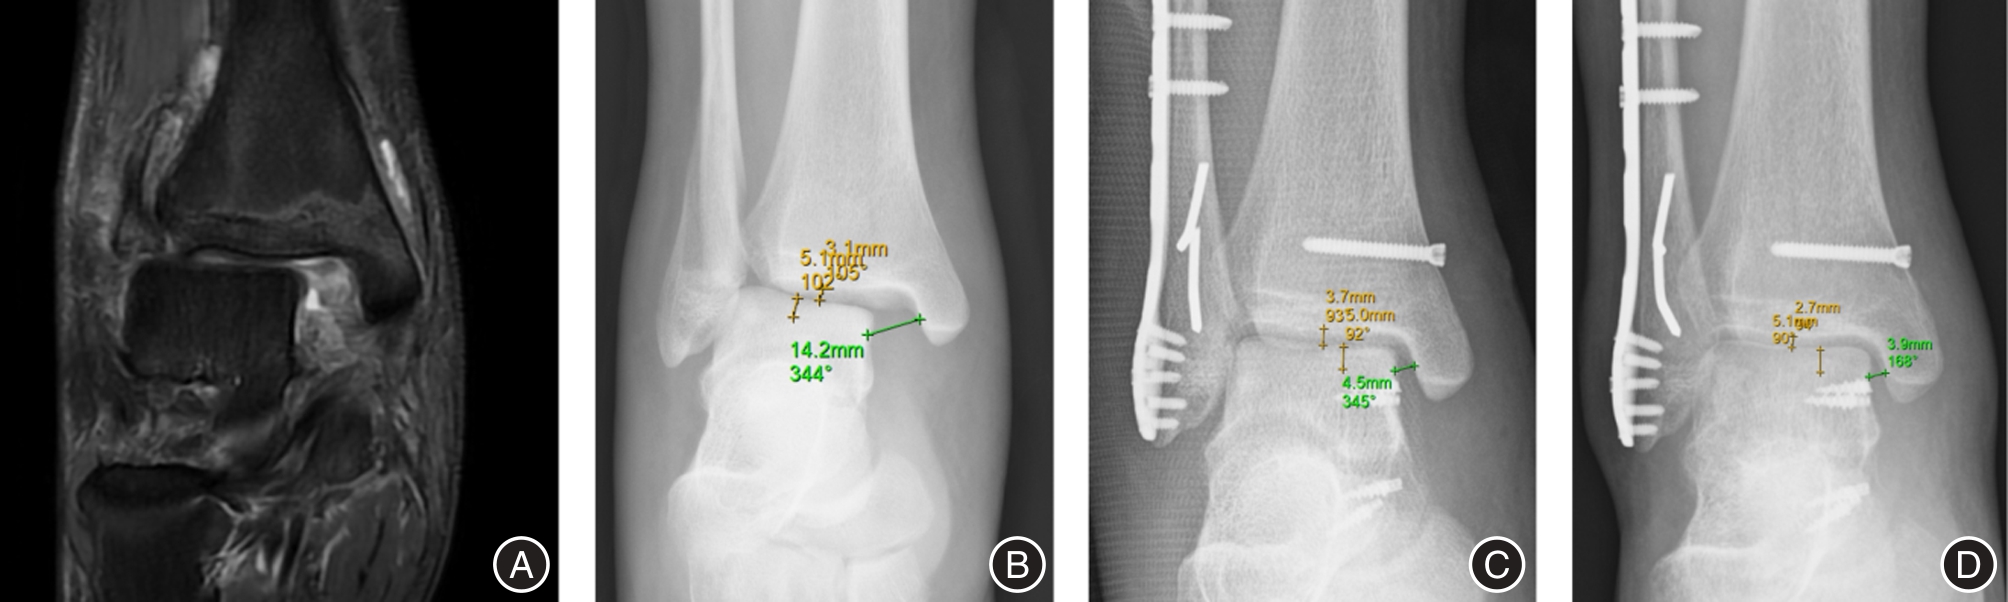

目的 探讨带线锚钉重建三角韧带(deltoid ligament)对踝关节骨折合并韧带损伤患者多维运动功能的影响。 方法 采用回顾性研究方法,纳入2023年3月至2024年3月期间在医院接受切开复位内固定术治疗的DL损伤合并关节骨折患者共210例。根据是否接受三角韧带重建分为重建组(110例)和对照组(单纯骨折固定,100例),其中重建组失访4例,对照组失访2例。比较两组术后优良率,并于术前及术后3、6、12个月评估六自由度(Six Degrees of Freedom,6DOF)运动参数、美国足踝外科协会评分(AOFAS)、疼痛视觉模拟评分(VAS)及影像学指标(间踝间隙和距骨倾斜角),同时记录术后并发症发生率。 结果 重建组手术时间、术中出血量和住院时间均显著高于对照组(P < 0.001)。术后12个月,重建组优良率显著高于对照组(93.40% vs. 81.63%,P < 0.05)。两组术后所有评估指标随时间持续改善,且重建组在踝关节6DOF运动参数(内旋/外旋、背伸/跖屈、内翻/外翻、上移/下移、内移/外移、前移/后移)、AOFAS评分及VAS评分方面改善程度均优于对照组(P < 0.001)。影像学结果显示,重建组间踝间隙及距骨倾斜角恢复更佳(P < 0.001)。两组术后并发症发生率差异无统计学意义(P > 0.05)。 结论 在关节骨折合并三角韧带损伤的治疗中,带线锚钉重建三角韧带可有效改善踝关节运动功能,提高AOFAS评分,减轻疼痛,促进影像学复位,且不增加术后并发症风险,是治疗此类损伤的安全有效方法。

Objective To investigate the impact of deltoid ligament reconstruction using suture anchors on multidimensional motor function in patients with ankle fractures combined with ligament injuries. Methods A retrospective cohort study included 210 patients undergoing open reduction and internal fixation (ORIF) for ankle fractures with confirmed DL injuries between March 2023 and March 2024. Based on intraoperative management of the DL, patients were allocated to a reconstruction group (received suture anchor-based DL reconstruction, n = 110; 4 lost to follow-up) or a control group (ORIF alone without DL reconstruction, n = 100; 2 lost to follow-up). Outcomes assessed preoperatively and at 3, 6, and 12 months postoperatively included: 6DOF ankle motion parameters (internal/external rotation, dorsiflexion/plantarflexion, inversion/eversion, superior/inferior translation, medial/lateral translation, anterior/posterior translation), American Orthopaedic Foot & Ankle Society (AOFAS) scores, visual analogue scale (VAS) pain scores, and radiographic parameters (medial clear space, talar tilt angle). Clinical efficacy at 12 months and postoperative complication rates were also compared. Results The reconstruction group demonstrated significantly longer operative times, greater intraoperative blood loss, and longer hospital stays compared to the control group (all P < 0.001). At 12-month follow-up, the excellent and good rate (based on AOFAS) was significantly higher in the reconstruction group (93.40% vs. 81.63%, P < 0.05). While all parameters improved significantly over time in both groups, the reconstruction group exhibited significantly greater improvements in all 6DOF motion parameters, higher AOFAS scores, and lower VAS scores at all postoperative time points (all P < 0.001). Radiographically, the reconstruction group achieved significantly better restoration of the medial clear space and talar tilt angle at all postoperative assessments (all P < 0.001). Postoperative complication rates did not differ significantly between the groups (P > 0.05). Conclusion For patients with ankle fractures combined with deltoid ligament injuries, suture anchor-based anatomical reconstruction of the deltoid ligament effectively restores multidirectional ankle kinematics, improves functional outcomes as measured by the AOFAS score, alleviates pain, and facilitates radiographic reduction, without increasing the risk of postoperative complications, thereby representing a safe and effective treatment strategy.